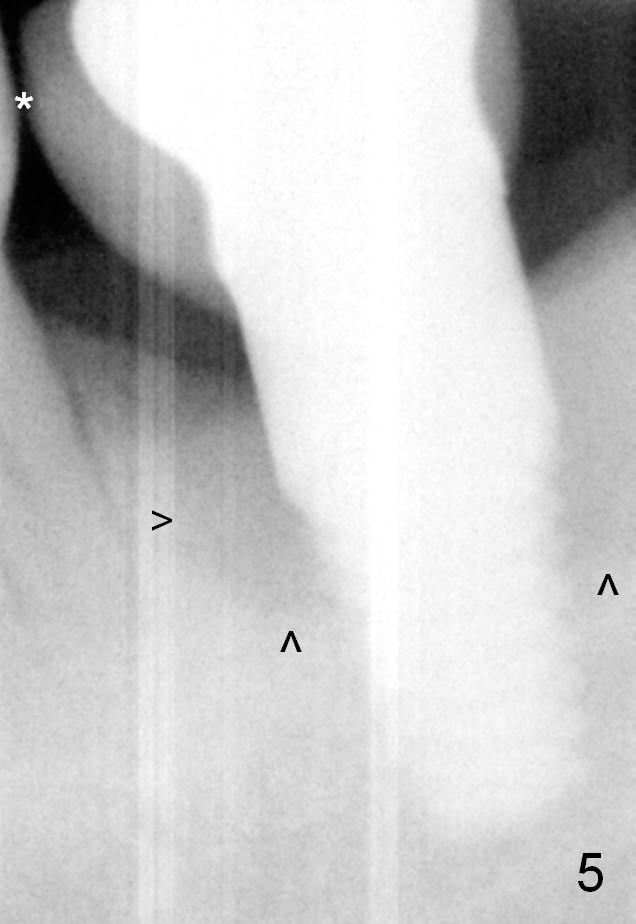

A 42-year-old man returns 3 years 10 months post implant crown cementation with chief complaint "food impaction is getting worse". In fact, the tooth #18 is lost due to chronic peridontitis (Fig.1). A 6x14 mm tissue-level implant is placed 4 months post extraction (Fig.2). Follow-up PA is taken 5 months postop before restoration (Fig.3).

The patient has never made an appointment for perio maintenance since implant placement. The most recent PA shows peri-implant bone loss increases mesially and extends distally (Fig.5 arrowheads). The open contact remains (*). Although there is no gingival erythema around the implant, the pockets appear to be deep.